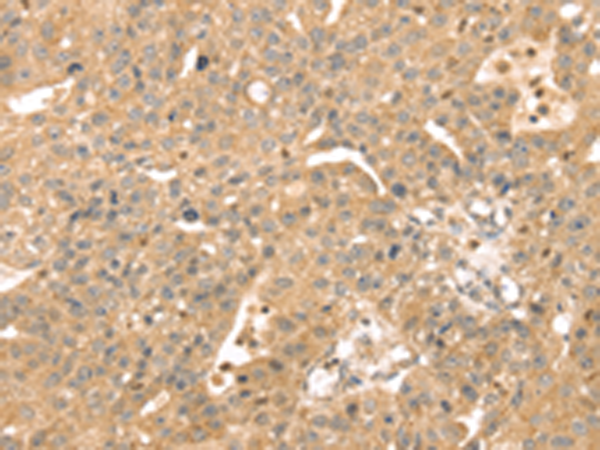

分类: 科研抗体货号: P01689别名: CATX-8; RAB11C应用: IHC反应种属: Human, Mouse